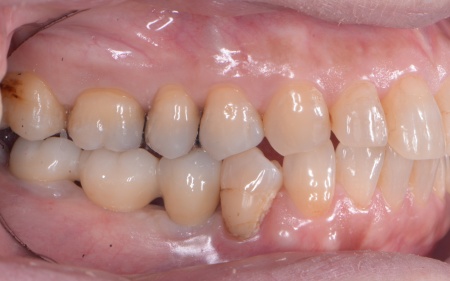

①入れ歯 ②インプラント それぞれのメリットとデメリットをお伝えしたところ、患者様は「できるだけ違和感がなく噛めるようになりたい。またなるべく短期間で治療を終えたい」と希望されたため、抜歯と同時にインプラントを埋め込む抜歯即時埋入法を提案し、同意いただきました。 まず、右下奥歯(第2小臼歯、第1大臼歯)を抜きます。 抜歯後にできた穴とインプラントの間には隙間が生じるため、骨の再生を助ける目的で骨補填材を使用しながら、丁寧に縫合しました。 3ヶ月後、インプラントと骨がしっかりと結合したことが確認できたため、被せ物を作製するための型取りを行います。 後日、完成した被せ物を装着し、見た目や噛み合わせに問題がないことを確認して、治療を終了しています。 |